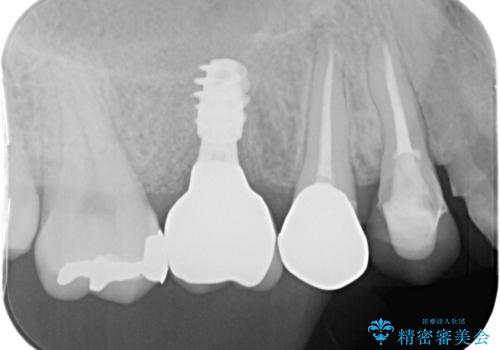

- 奥歯で噛んだ時の違和感を主訴に来院された患者様です。

歯根の先端の病変が大きく割れてしまっていた為、抜歯の必要がありました。

レントゲン等、検査を行ったところ骨の厚みは問題ないですが、

高さは少し低かったので、幅が太い短いインプラントを使って治療を行う計画を立てました。

インプラント治療により問題無く奥歯で噛めるようになりましたが、奥歯の噛み合わせが強いためインプラント周囲の骨吸収や他の歯の破折等が起きる可能性があります。

夜間就寝時のマウスピース装着、定期的なメンテナンスでレントゲン、噛み合わせの確認は必須です。